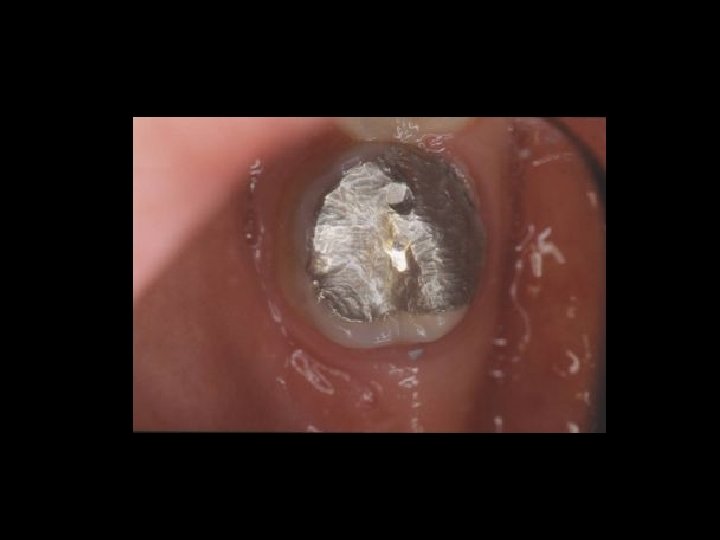

Responsabilità Ø Restauro della corona del dente Ø Trattamenti radicolari